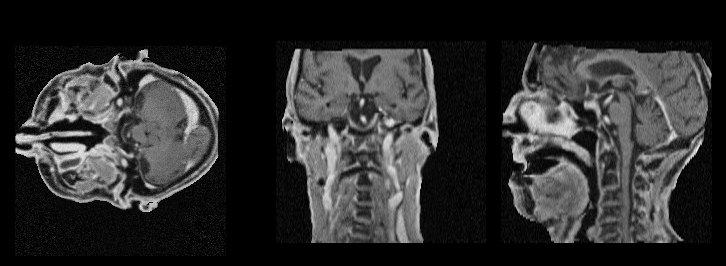

MIND: Neural Dose Engine

A proof-of-concept neural engine that predicts individual proton pencil beam dose distributions directly from MRI. A Transformer-based model operating on beam’s-eye-view patches achieves Monte Carlo-comparable accuracy (median 99.8% gamma pass rate at 1 mm/1%) while reducing computation time to about 3 ms per beam (a 600x speedup over FRED MC on GPU).

A proof-of-concept study of direct magnetic resonance imaging-based proton dose calculation for brain tumors via neural networks with Monte Carlo-comparable accuracy

Muheng Li, Carla Winterhalter, Xia Li, Sairos Safai, Antony Lomax, Ye Zhang

Physics and Imaging in Radiation Oncology (phiRO), 2025

Presents the MIND neural dose engine that predicts individual proton pencil beam dose distributions directly from MR images, achieving a median 99.8% gamma pass rate at 1 mm/1% while reducing computation to about 3 ms per beam.